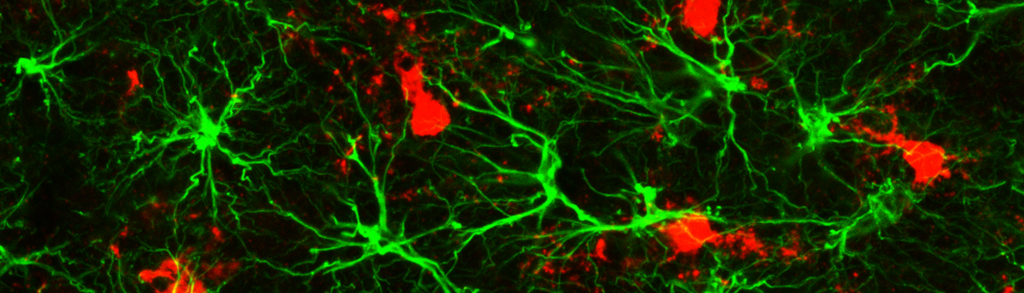

There is growing awareness that a common hallmark of neurological and psychiatric diseases is synaptic dysfunction. The Unit’s main focus is to evaluate how neurons, glial cells, and synapses are modulated, and how these processes are altered in disease states or restored by potential therapeutics. Current research addresses dysfunctions in various types of epilepsy, synaptic circuitry remodeling after stroke and seizures, synaptic reorganization following chronic drug abuse and/or depression, and functional alterations of neurons, glial cells, and synapses at the onset of neurodegenerative diseases such as amyotrophic lateral sclerosis, multiple sclerosis, and Alzheimer’s disease.

We aim to understand these dysfunctions at the synaptic and neuronal circuitry levels and to identify novel strategies that may pave the way for the discovery of more effective therapeutics.